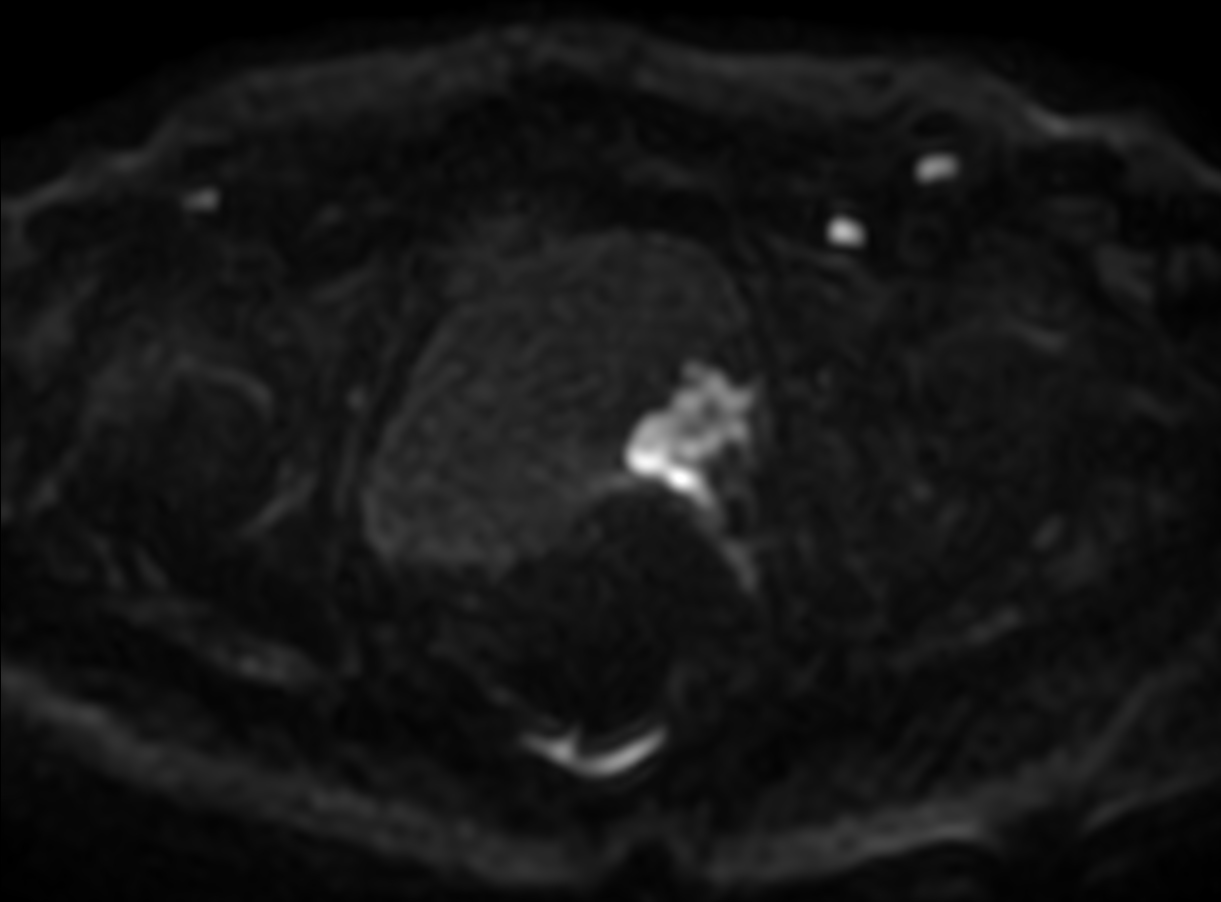

Patient with bladder cancer. The ExamCard includes techniques for motion reduced imaging (MultiVane XD), 3D TSE imaging (PelvisVIEW) allowing for multiple image directions in one single scan, a multi-phase contrast-enhanced sequence (4D FreeBreathing) to improve imaging confidence and Compressed SENSE to accelerate the entire exam.

DWI b1200

DWI b1200 (ADC)